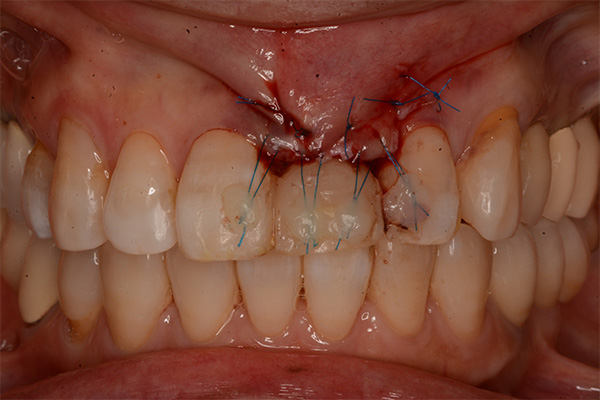

抜歯9ヶ月後(左)歯肉にヘコみができているので手術で歯肉を増大させる

2週間後、赤みは残るが歯肉の厚みは増えた(右)

左隣りの歯の裏側を削る切削量は最小限

装着時、歯肉は左右対称に近い感じになる